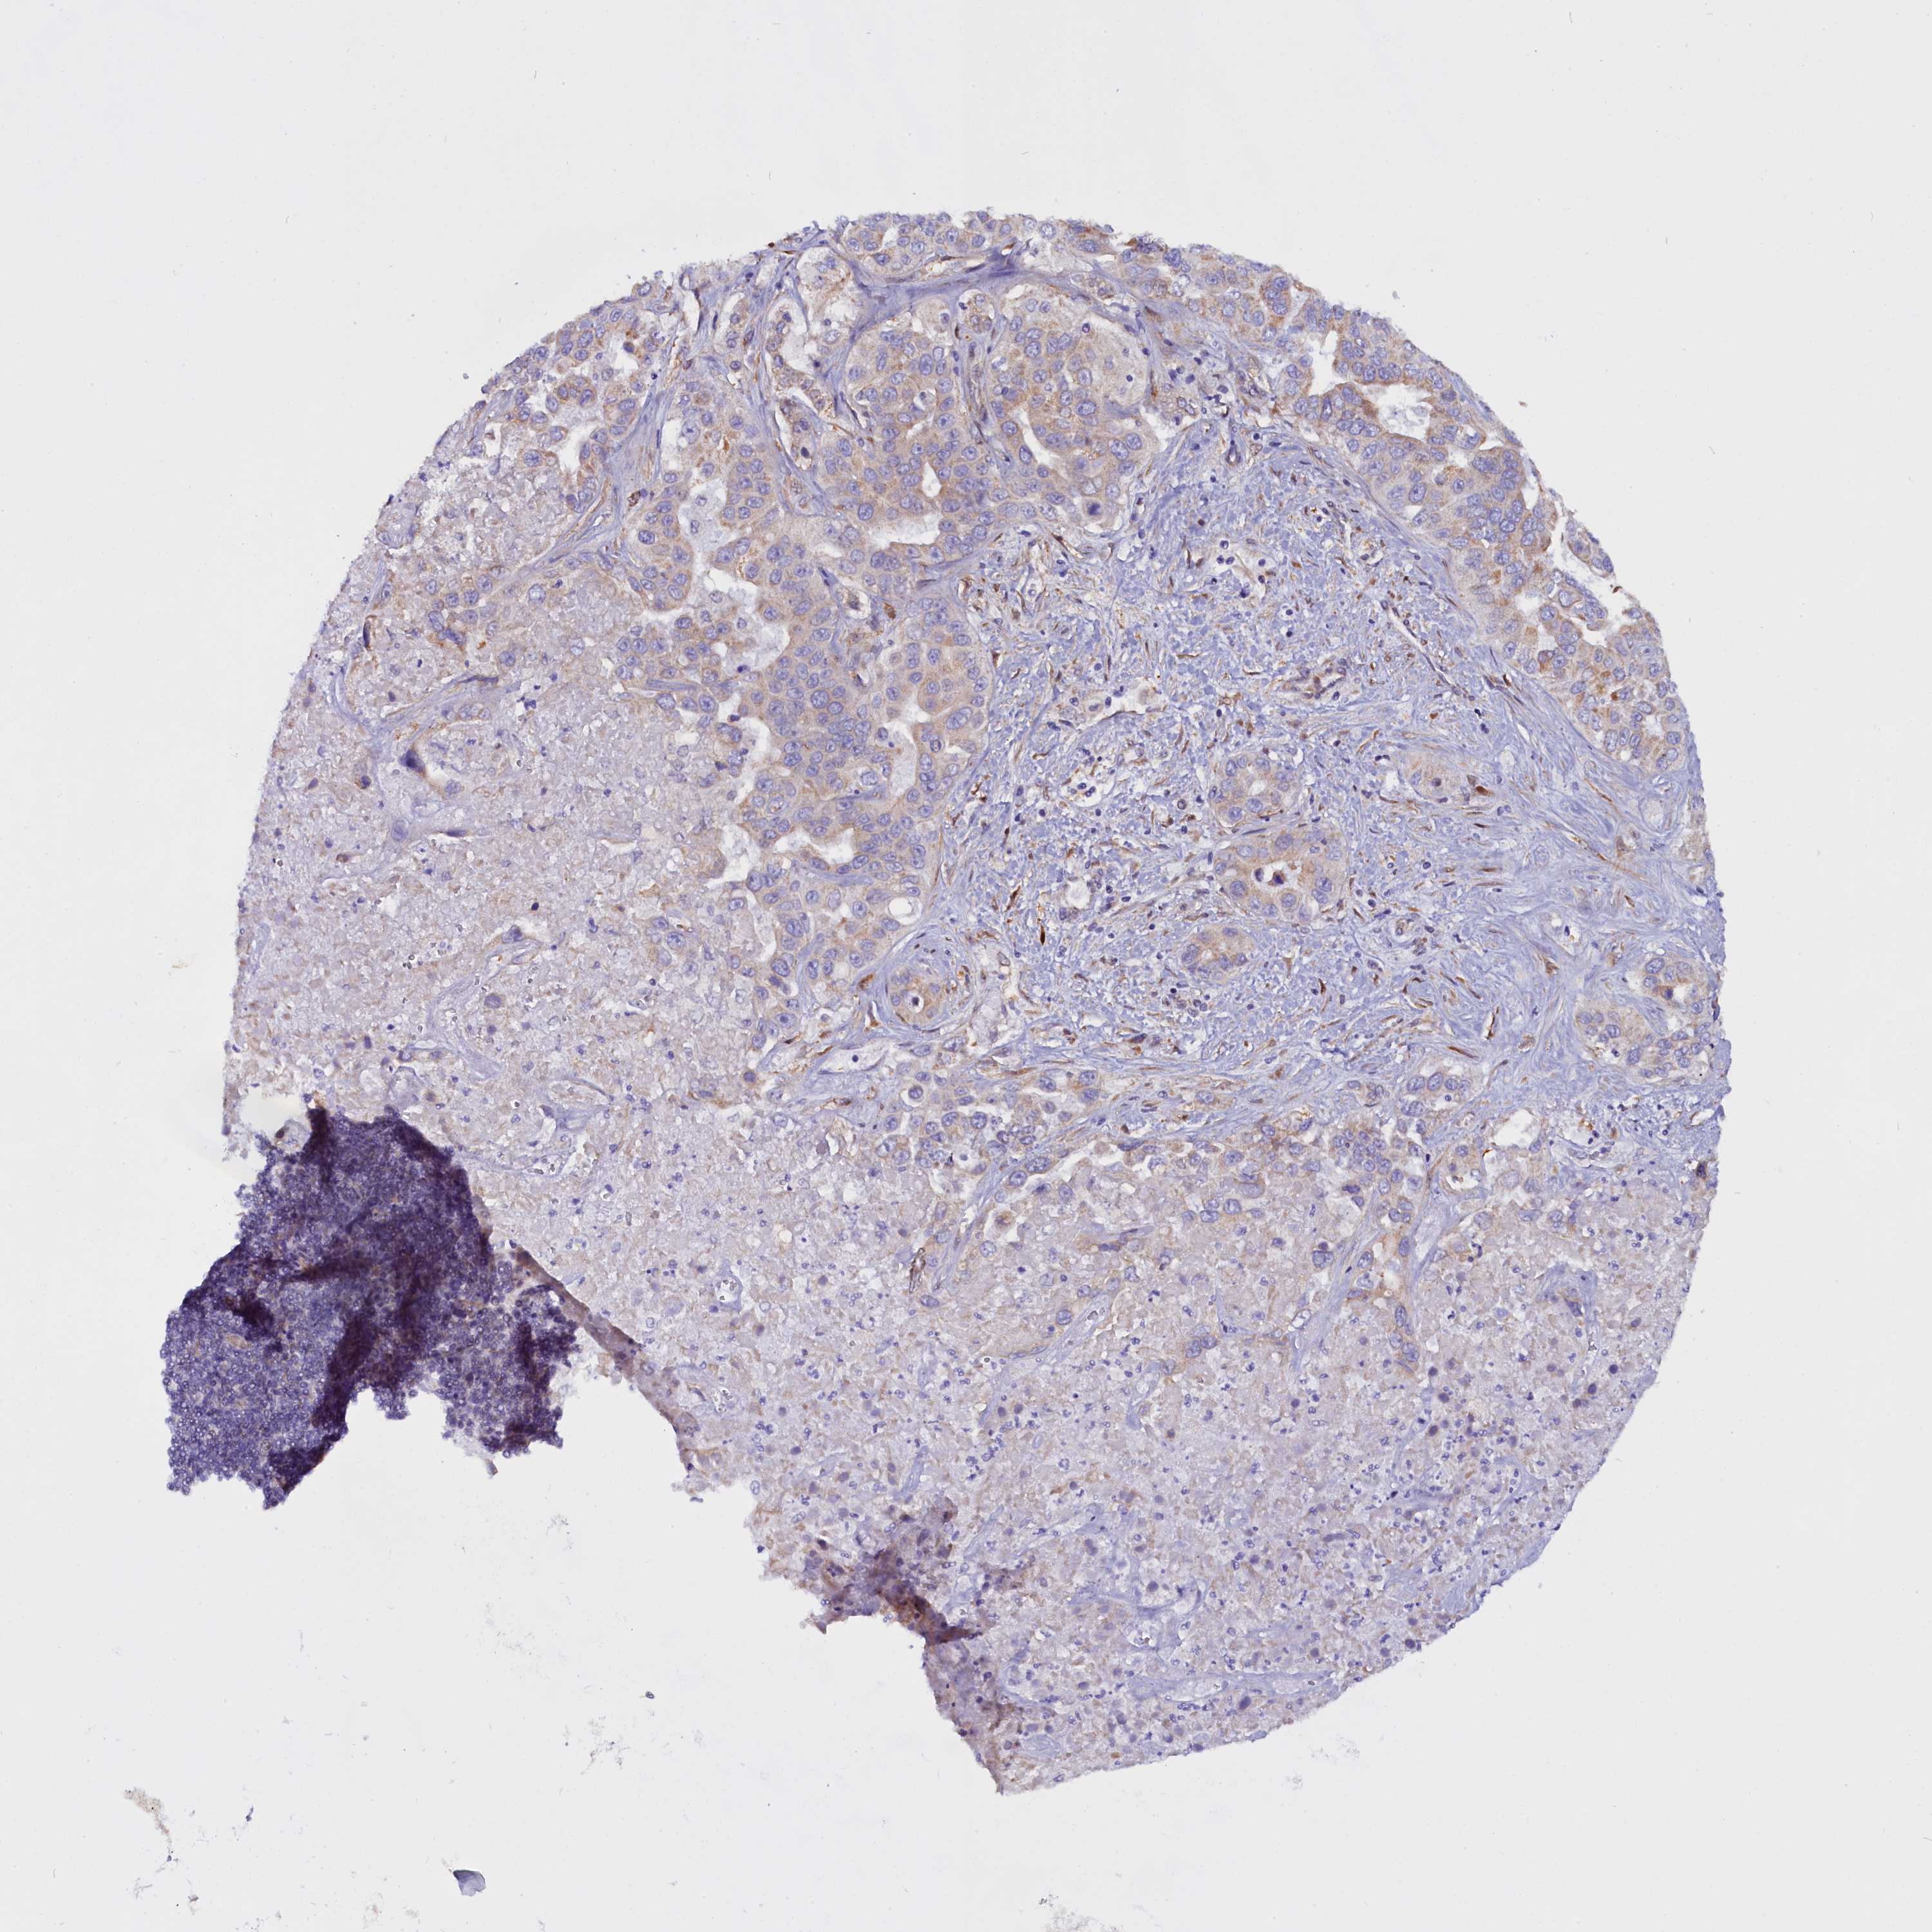

LIVER CANCER - Protein expressioni

A mouse-over function shows sample information and annotation data. Click on an image to view it in a full screen mode. Samples can be filtered based on level of antibody staining by selecting one or several of the following categories: high, medium, low and not detected. The assay and annotation is described here.

Note that samples used for immunohistochemistry by the Human Protein Atlas do not correspond to samples in the TCGA dataset.

Antibody stainingi

Antibody staining in the annotated cell types in the current human tissue is reported as not detected, low, medium, or high, based on conventional immunohistochemistry profiling in selected tissues. This score is based on the combination of the staining intensity and fraction of stained cells.

Each image is clickable and will lead to virtual microscopy that enables deeper exploration of all samples and also displays staining intensity scores, fraction scores and subcellular localization as well as patient and tissue information for each sample.

Antibody HPA041412

Antibody HPA056006

Staining

High

Medium

Low

Not detected

Intensity

Strong

Moderate

Weak

Negative

Quantity

>75%

75%-25%

<25%

None

Location

Nuclear

Cytoplasmic/membranous

Cytoplasmic/membranous,nuclear

Cholangiocarcinoma

Carcinoma, Hepatocellular, NOS